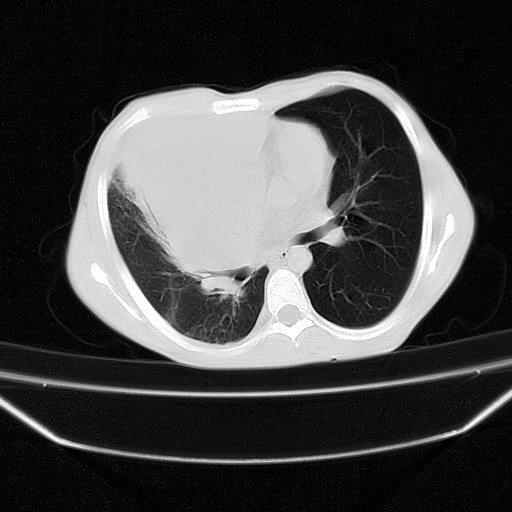

以下是引用zjzjr在2008-7-20 12:57:00的发言:[br]考虑为生殖源性肿瘤(内胚窦瘤),侵袭性胸腺瘤可能性大;右侧少量胸腔积液。

以下是引用xinliheng001在2008-7-20 21:17:00的发言:[br]右纵隔巨大分叶状软组织均质密度肿块,右上肺叶受压明显,纵隔右移、胸膜受累有少量积液和结节样增厚。应增强扫描一定会有更具诊断价值的信息。

以下是引用xinliheng001在2008-7-20 21:17:00的发言:[br]右纵隔巨大分叶状软组织均质密度肿块,右上肺叶受压明显,纵隔右移、胸膜受累有少量积液和结节样增厚。应增强扫描一定会有更具诊断价值的信息。